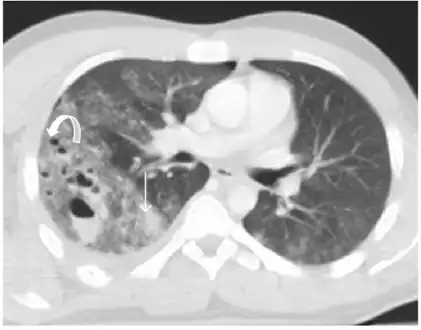

Coronal CT scan showing lucencies (pale areas in radiography) in the lung caused by pulmonary lacerations on the left of the image (black arrows)

Pulmonary laceration may not be visible using chest X-ray because an associated pulmonary contusion or hemorrhage may mask it.[1][9] As the lung contusion clears (usually within two to four days), lacerations begin to become visible on chest X-ray.[3] CT scanning is more sensitive and better at detecting pulmonary laceration than X-rays are,[1][5][12][15] and often reveals multiple lacerations in cases where chest X-ray showed only a contusion.[12] Before CT scanning was widely available, pulmonary laceration was considered unusual because it was not common to find with X-ray alone.[12] On a CT scan, pulmonary lacerations show up in a contused area of the lung,[9] typically appearing as cavities filled with air or fluid[16] that usually have a round or ovoid shape due to the lung's elasticity.[4]

Hematomas appear on chest radiographs as smooth masses that are round or ovoid in shape.[1] Like lacerations, hematomas may initially be hidden on X-ray by lung contusions, but they become more apparent as the contusion begins to heal.[1] Pneumatoceles have a similar shape to that of hematomas but have thin, smooth walls.[17] Lacerations may be filled completely with blood, completely with air, or partially with both.[4] Lacerations filled with both blood and air display a distinctive air-fluid level.[4] A single laceration may occur by itself, or many may be present, creating an appearance like Swiss cheese in the radiography of the lung.[4]